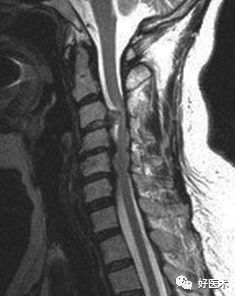

诊断